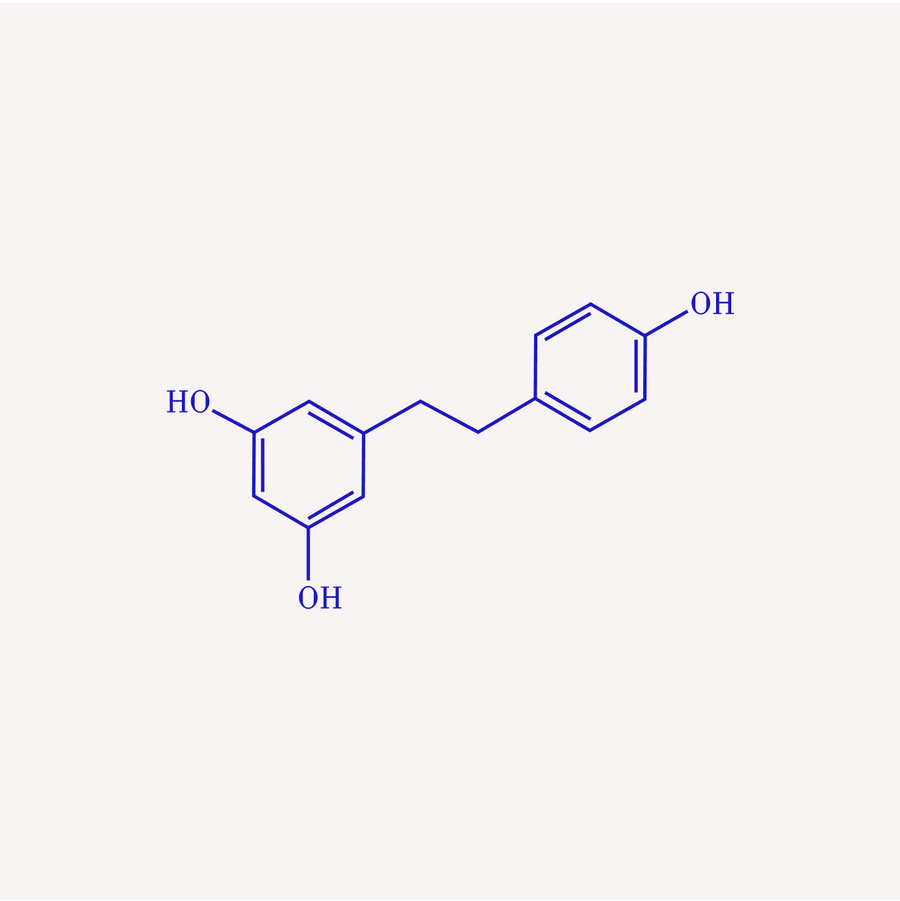

Resveratrol & Quercetin

Activate sirtuins, reduce oxidative stress, and clear damaged cells.

Wong RH, Thaung Zaw JJ, Xian CJ, Howe PR. Regelmäßige Nahrungsergänzung mit Resveratrol verbessert die Knochenmineraldichte bei postmenopausalen Frauen: Eine randomisierte, placebokontrollierte Studie. J Bone Miner Res. 2020 Nov;

Mahjabeen W, Khan DA, Mirza SA. Rolle der Resveratrol-Supplementierung bei der Regulierung der Glukosehämostase, Entzündungen und des oxidativen Stresses bei Patienten mit Diabetes mellitus Typ 2: Eine randomisierte, placebokontrollierte Studie. Complement Ther Med. 2022 Jun;

nchingolo AD, Inchingolo AM, Malcangi G, Avantario P, Azzollini D, Buongiorno S, Viapiano F, Campanelli M, Ciocia AM, De Leonardis N, de Ruvo E, Ferrara I, Garofoli G, Montenegro V, Netti A, Palmieri G, Mancini A, Patano A, Piras F, Marinelli G, Di Pede C, Laudadio C, Rapone B, Hazballa D, Corriero A, Fatone MC, Palermo A, Lorusso F, Scarano A, Bordea IR, Di Venere D, Inchingolo F, Dipalma G. Auswirkungen der Resveratrol-, Curcumin- und Quercetin-Supplementierung auf den Knochenstoffwechsel – eine systematische Übersicht. Nährstoffe. 26.08.2022;

Mohammadipoor N, Shafiee F, Rostami A, Kahrizi MS, Soleimanpour H, Ghodsi M, Ansari MJ, Bokov DO, Jannat B, Mosharkesh E, Pour Abbasi MS. Resveratrol- Supplementierung verbessert effizient die endotheliale Gesundheit: Eine systematische Überprüfung und Metaanalyse randomisierter kontrollierter Studien. Phytother Res. 2022 Sep;

Tosatti JAG, Fontes AFDS, Caramelli P, Gomes KB. Auswirkungen einer Resveratrol- Supplementierung auf die kognitive Funktion von Patienten mit Alzheimer-Krankheit: Eine systematische Überprüfung randomisierter kontrollierter Studien. Drugs Aging. 2022 Apr;

Kohandel Z, Darrudi M, Naseri K, Samini F, Aschner M, Pourbagher-Shahri AM, Samarghandian S. Die Rolle von Resveratrol bei Alterung und Seneszenz: Ein Fokus auf molekulare Mechanismen. Curr Mol Med. 2024;

Thaung Zaw JJ, Howe PR, Wong RH. Langzeiteffekte von Resveratrol auf Kognition, zerebrovaskuläre Funktion und kardio-metabolische Marker bei postmenopausalen Frauen: Eine 24-monatige randomisierte, doppelblinde, placebokontrollierte Crossover-Studie. Clin Nutr. 2021 März;

Zhou DD, Luo M, Huang SY, Saimaiti A, Shang A, Gan RY, Li HB. Auswirkungen und Mechanismen von Resveratrol auf das Altern und altersbedingte Erkrankungen. Oxid Med Cell Longev. 11. Juli 2021;

Breuss JM, Atanasov AG, Uhrin P. Resveratrol und seine Auswirkungen auf das Gefäßsystem. Int J Mol Sci. 2019 Mar 27;